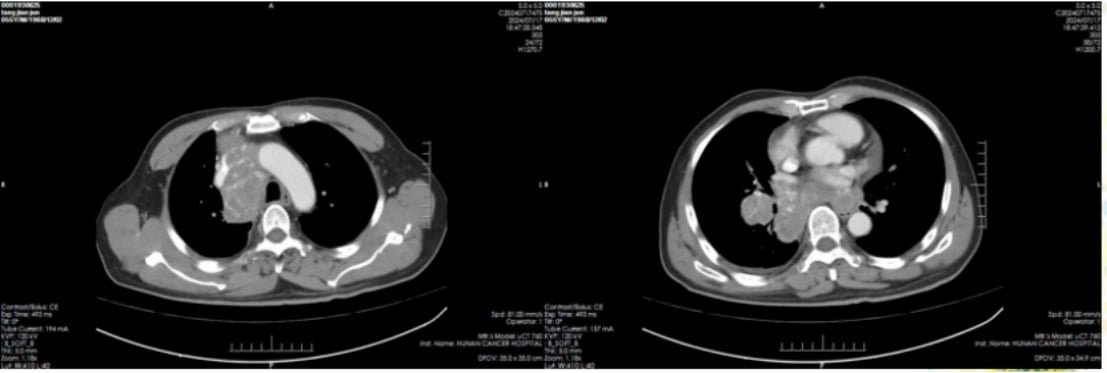

肺部病灶变化:

治疗前(2024-5-14),右肺门区可见明显肿块。治疗后(2024-7-17),右下肺门区肿块较前显著缩小,阻塞性肺炎及肺不张得到缓解,纵隔转移淋巴结也明显缩小,胸腔积液减少。

图1:治疗前肺部影像

图2:治疗后肺部影像